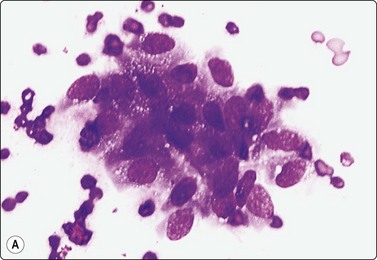

Adenocarcinoma of prostate (Figs 13.5-13.8)4,5,27,34,36,37,39

image image image

Fig. 13.5 Well-differentiated adenocarcinoma

Cohesive sheets of atypical glandular epithelium; mild nuclear enlargement and anisokaryosis; crowding of nuclei; absence of cytoplasmic granules. Note microacinar pattern in B and prominent nucleoli and a mitotic figure in C (A and B, DQ; C, Pap, HP).

In smears of prostatic carcinoma, sheets of benign glandular epithelial cells are commonly seen side-by-side with aggregates of malignant cells (Fig. 13.6), reflecting the diffusely infiltrative growth of the tumor. Benign and malignant cells can be directly compared (very helpful clue) and differences in cytoarchitectural features are easily appreciated. Nuclear enlargement is one of the most important criteria of malignancy. Nucleolar enlargement is better demonstrated in Pap-stained smears.

Absence of visible cell membranes, nuclear crowding and overlapping and dissociation of cells are other important criteria. The presence of coarse intracytoplasmic secretory granules makes malignancy unlikely, but they can occasionally be found in cells from well-differentiated adenocarcinoma. Cytoplasmic vacuolation may be seen in both benign and malignant cells. Nuclear pleomorphism and chromatin abnormalities are obvious in less well-differentiated cancers but may be subtle in well-differentiated carcinomas, rendering a definitive malignant diagnosis difficult (Fig. 13.5). Demonstration of basal epithelial cells by immunocytochemistry may be of help in the distinction between well-differentiated adenocarcinoma and adenosis or basal cell hyperplasia,5 but interpretation is more difficult than in histologic sections. Immunostaining is a useful tool for the diagnosis of prostate cancer at metastatic sites.42 Results may be conflicting in metastases of poorly differentiated carcinomas.